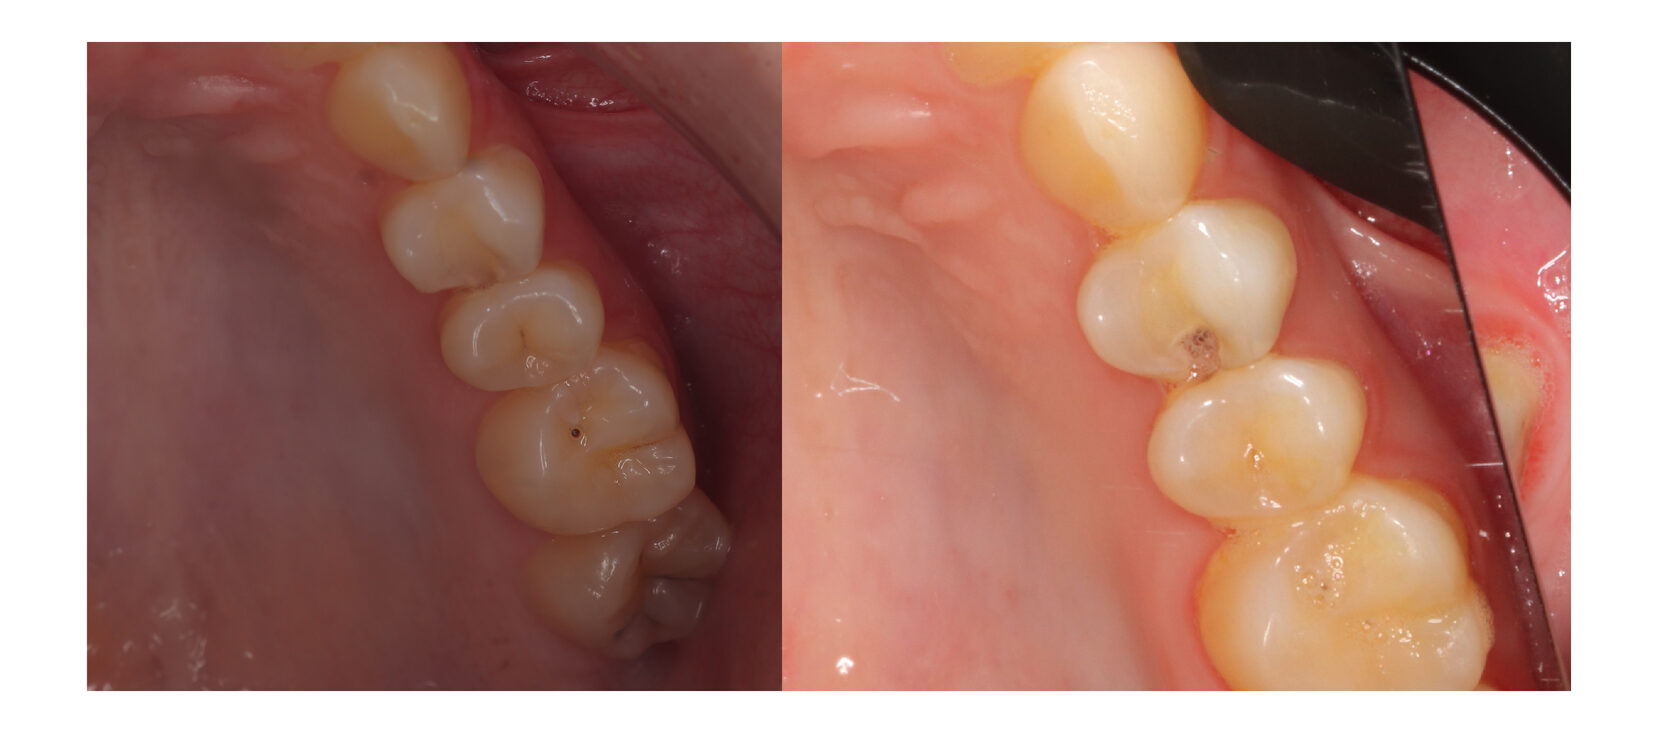

Эндодонтическое лечение проводилось согласно клинических рекомендаций ВОЗ и протоколов нашего центра. Корневые каналы промыты, избавлены от очага инфекции и плотно запломбированы, что подтверждается на контрольном снимке.

Самый главный вывод из этой работы, это, конечно, то, что все возникающие проблемы и кариозные процессы необходимо решать своевременно, для того, чтобы не было обострений и неприятных последствий. Ну, а мы сделаем все качественно и сохраним всё, что будет возможно!